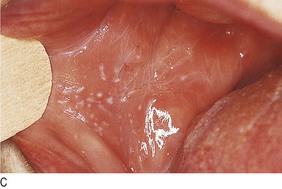

• Wrist lesions suggest lichen planus (Fig. 4.6). Look at the buccal mucosa for the white lacy lesions of Wickham’s striae to confirm this.

Fig. 4.6 Diagnostic sequence, lichen planus.

(A) Discrete flat-topped papules on the wrist. (B) Wickham’s striae visible on close inspection. (C) White lacy network of striae on buccal mucosa.